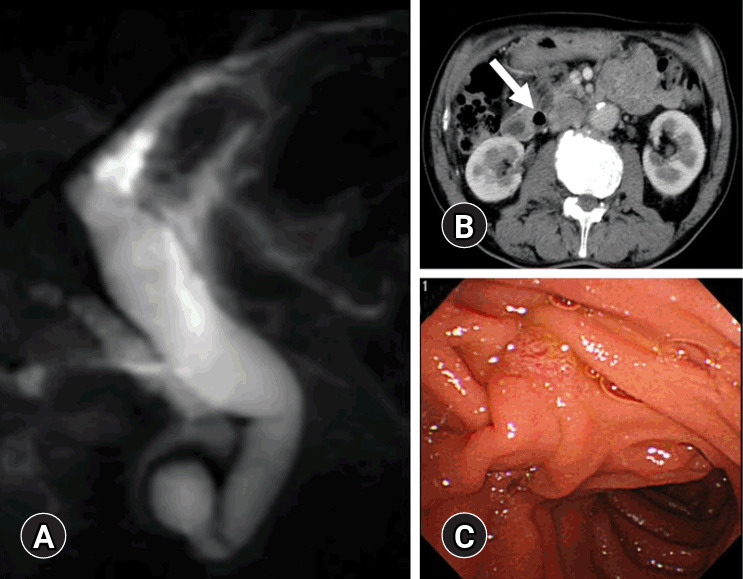

An unusual cause of acute obstructive suppurative cholangitis.

急性梗阻性化脓性胆管炎的罕见病因。